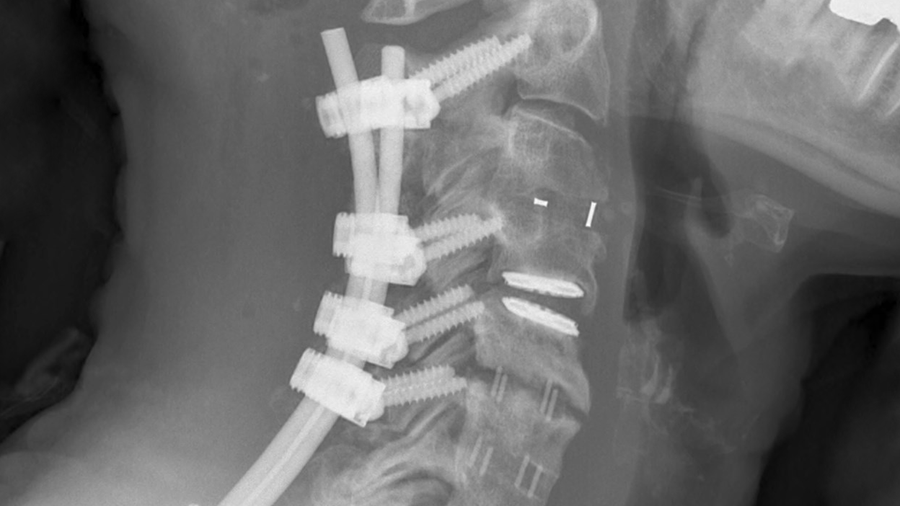

The AO Technical Commission is proud to announce the Cervical Expert Group as well-deserved winners of the 2021 Innovation Prize. Awarded for advancements in Posterior Cervical Fusion (PCF) and development of the Symphony Occipito-Cervico-Thoracic System, the prize acknowledges clinical innovation apparent in a solution that successfully addresses deformity correction, revision surgery and fixation in poor quality bone (Fig 1). Discussions about the need for such a system were initiated during a 2014 Cervical Expert Group meeting. After years of development Symphony was introduced in a teaching capacity during the 2019 Complex Cervical Course in Davos (Fig 2). The Cervical Expert Group is an international group of expert spine surgeons, and the AO Technical Commission congratulates them for their achievements in advancing the care of patients requiring fixation of the cervical spine.

Fig 1 Symphony Occipito-Cervico-Thoracic System.